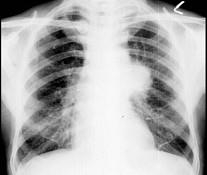

问题 60岁,男,有长期抽烟史,左声带麻痹、声音嘶哑2个月,请结合胸片和CT图,选出最可能的诊断 ( )

选项 A.肺癌 B.肺结核 C.尘肺 D.肺炎 E.肺结节病

答案 A